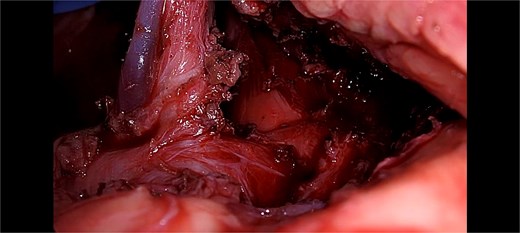

After multidisciplinary clinic-radiological discussion, the patient was counseled and consent was taken for Laparoscopic intervention. She underwent laparoscopic release of the median arcuate ligament. The intra-operative findings were thick fibrous bands of median arcuate ligament crossing over the celiac trunk, and indenting it antero-posteriorly at its origin from abdominal aorta. The fibrous band of meadian arcuate ligament were released from celiac trunk. The segment distal to compressed segment pulsations of celiac artery showed return of normal pulsations (Fig. 2). The post-operative course was uneventful. Her symptoms significantly improved by the second postoperative week, and she began regaining weight at 1-month follow-up.

Showing intra-operative thick fibrous bands of median arcuate ligament crossing over the celiac trunk.